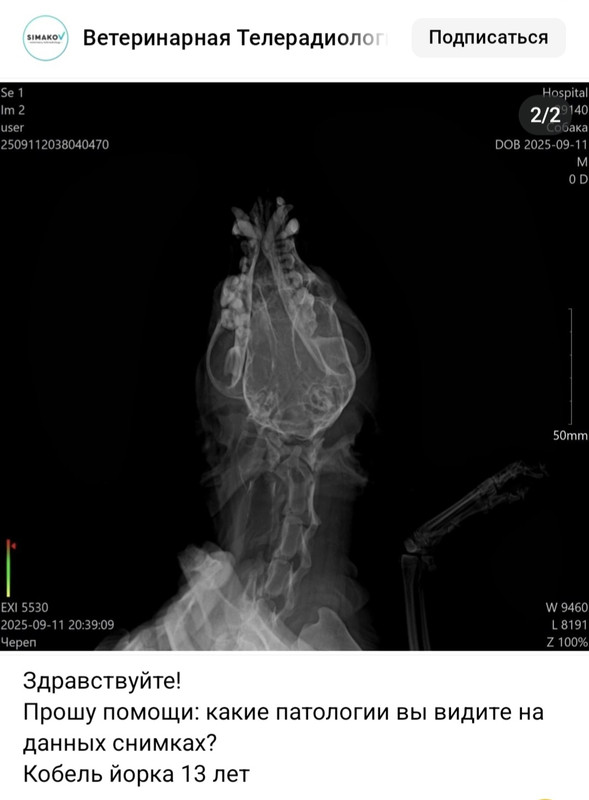

Новые подробности о Йорке.

https://vk.com/wall-222901296_6145

у собаки с "размозженным черепом" и "погруженной в искуственную кому" в описании снимков нет никаких повреждений,только патологические возрастные изменения.